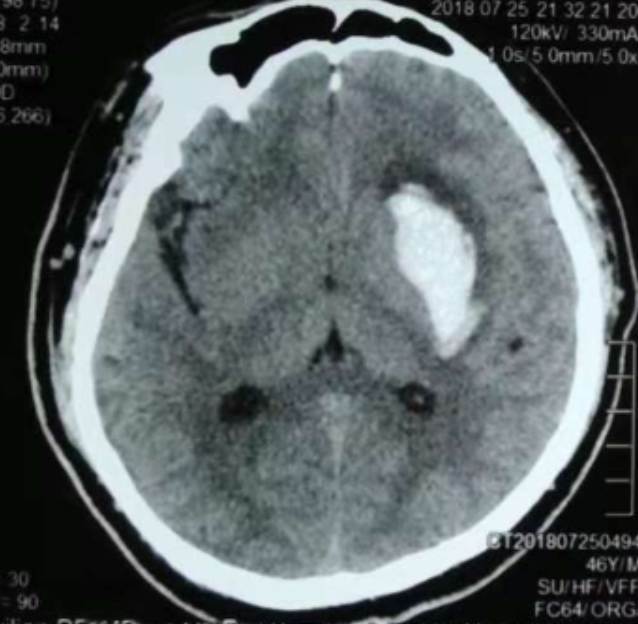

術(shù)前CT:血腫已經(jīng)液化,但仍有占位效應(yīng)